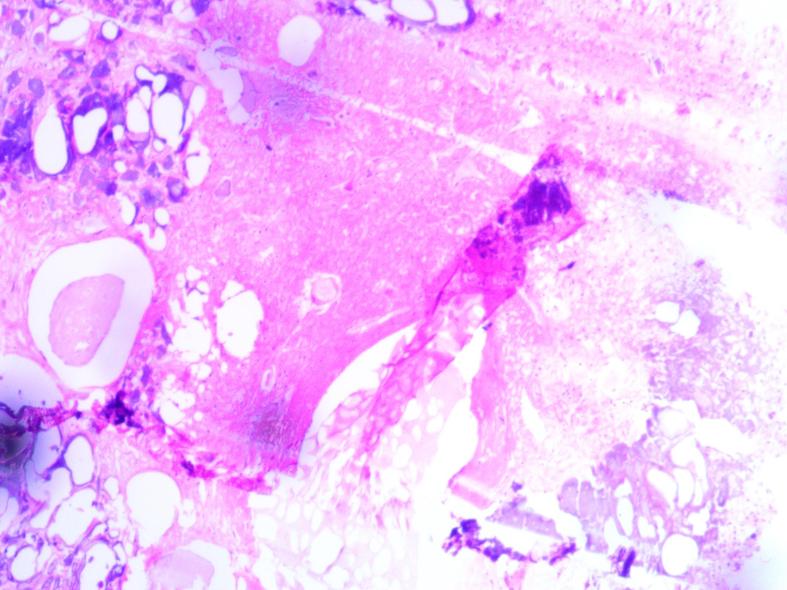

Idiopathic scrotal calcinosis is a rare condition characterized by calcium deposition in the skin of the scrotum. We present a case of a 67-year-old male patient with idiopathic scrotal calcinosis, a rare condition characterized by calcium deposition in the skin of the scrotum. The patient initially noticed multiple nodular masses on his scrotum 30 years ago, which gradually increased in size and caused discomfort. Physical examination and enhanced CT scans revealed multiple, well-demarcated high-density nodules on the skin surface of the scrotum. The patient underwent surgical resection of the lesions, and histopathological findings confirmed the diagnosis of idiopathic skin calcium deposition in the scrotum.

特发性阴囊钙化症是一种罕见病症,其特征为阴囊皮肤出现钙沉积。我们报告一例67岁男性特发性阴囊钙化症患者,该病症以阴囊皮肤钙沉积为特征。患者30年前最初注意到阴囊上有多个结节状肿物,肿物逐渐增大并引起不适。体格检查和增强CT扫描显示阴囊皮肤表面有多个边界清晰的高密度结节。患者接受了病变手术切除,组织病理学检查结果证实为阴囊特发性皮肤钙沉积。

讨论

特发性阴囊钙化症(ISC)是一种罕见的良性外科皮肤疾病,主要累及阴囊皮肤。其特征是钙在真皮中自发沉积,导致形成多个无症状的钙化结节。ISC通常根据临床表现诊断,并通过组织学检查确诊。ISC手术治疗效果良好。